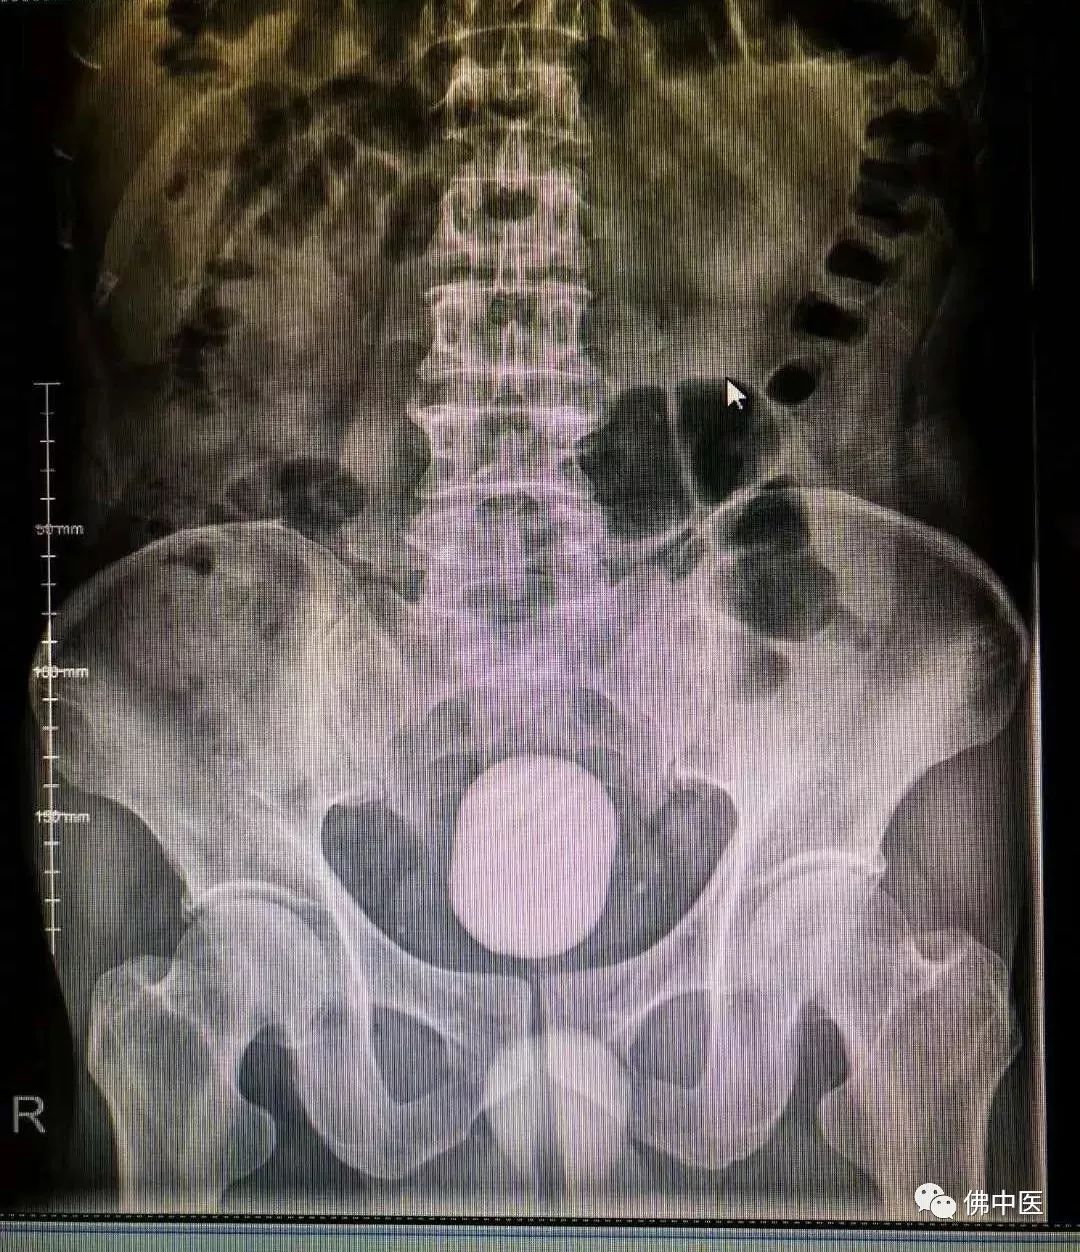

取出了6*7*5cm大小的结石

钟羽翔表示,由于老人膀胱结石巨大,经科室讨论决定实施开放手术,切开取石。不到半个小时,钟羽翔便从患者腹部掏出一个巨大的膀胱结石,最大径长7cm。

尽管膀胱结石形成因素是综合性的,但是随着医疗条件的不断改善,一般通过常规的体检、临床表现、B超、X线检查等,膀胱结石大多还是能早期诊断、早期治疗,难以发展成膀胱巨大结石,目前常见的膀胱结石通常直径在3cm左右,本例的老人能形成如此巨大膀胱结石,实属罕见。